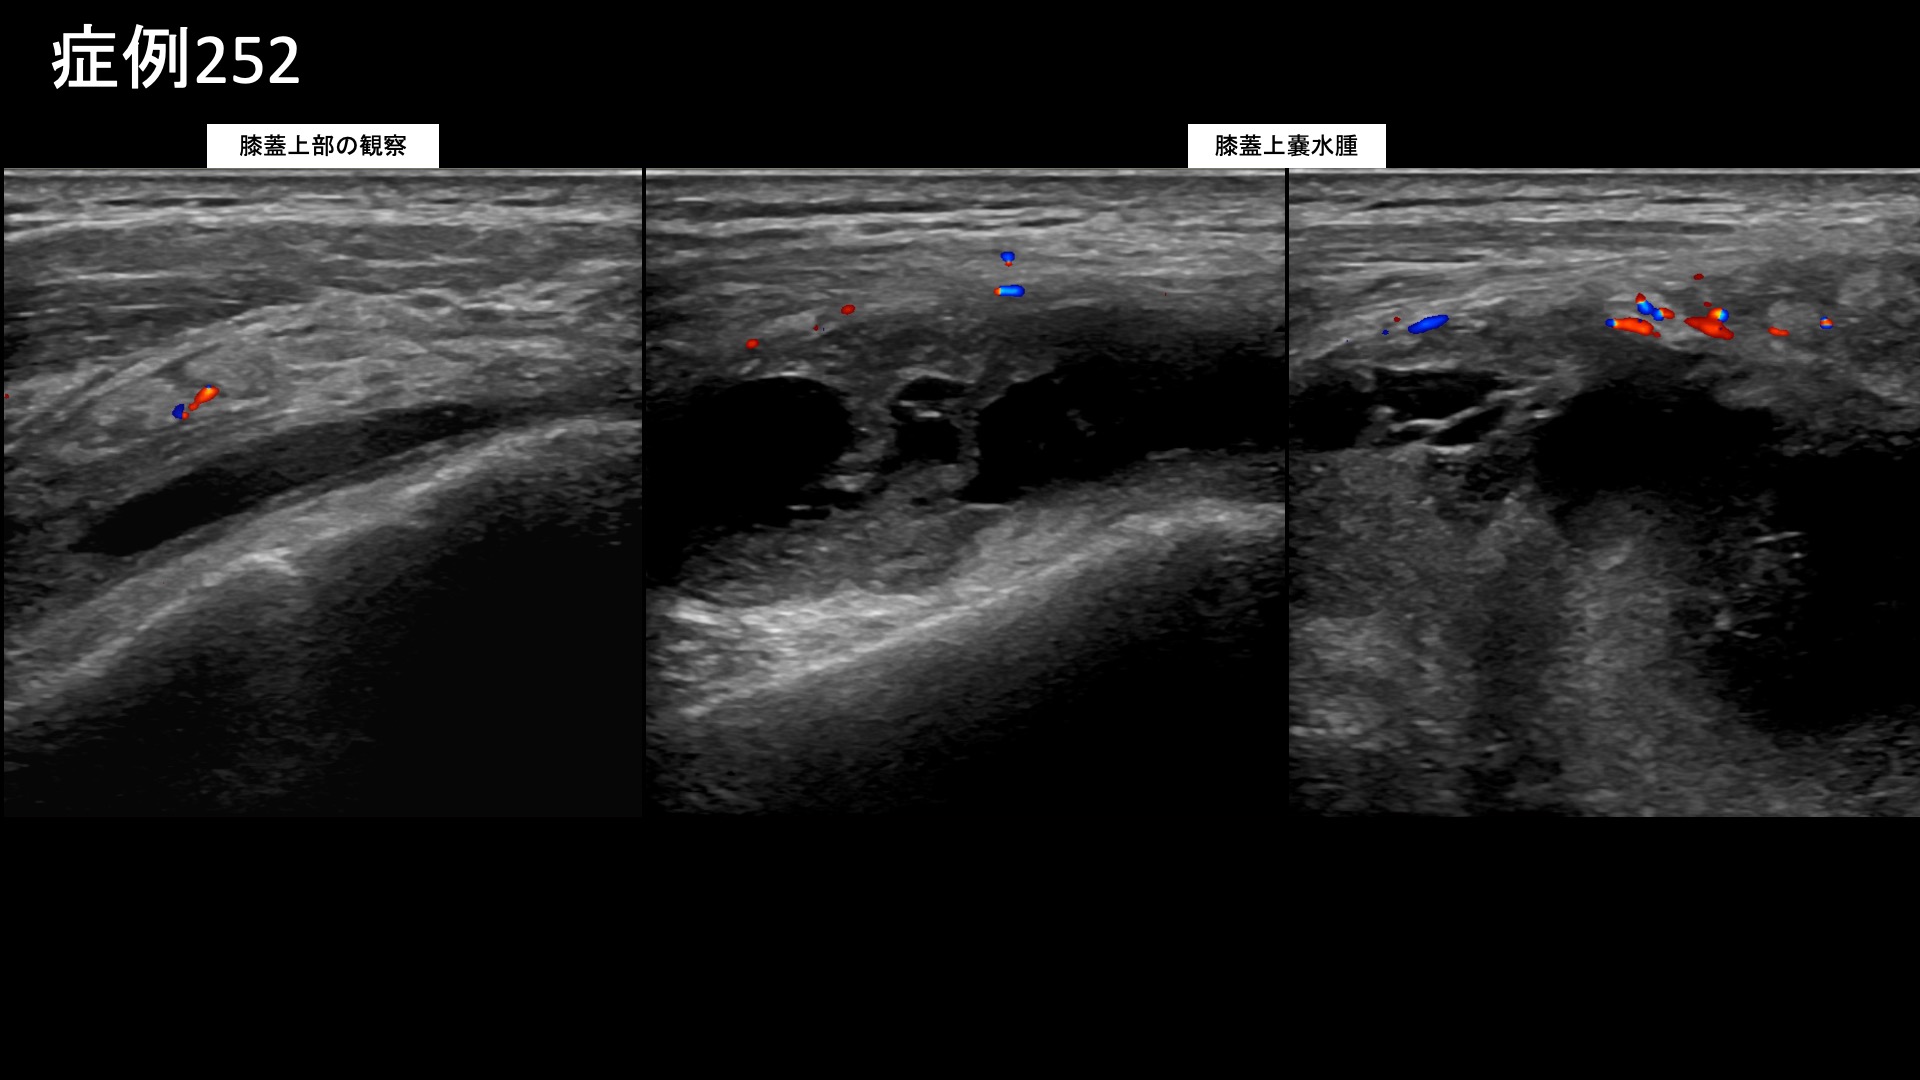

膝:変形性膝関節症など 【70代:男性】急激に悪化した膝の痛みで歩けなくなり夜も寝られず水も溜まる・・ネフローゼ症候群を合併した変形性膝関節症の実例(変形性膝関節症、ネフローゼ症候群) 2025.12.01 鴨井院長による動画解説 受診までの経過 それまで痛めたことはなかったのですが、3ヶ月前から急に右膝が痛み始めました。整形外科を受診し、水を抜いてもらいヒアルロン酸注射を受けていましたが改善しませんでした。松葉杖を使うほどの痛みにもなり、安静時にも痛むようになりました。ついには夜間に痛みで目が覚めるほどになりました。鎮痛薬も効かない一方で、外科手術の適応ではないと言われ思い悩んでいたところ、当院の治療を知り受診されました。 既往疾患;ネフローゼ症候群 診察時の所見 杖歩行にて入室されました。レントゲンでは中等度以上(KL分類3相当)の関節変形を認めました。エコー検査では、膝蓋上嚢に中等度以上の水腫を認め、その周囲や滑膜組織には炎症によるモヤモヤ血管を反映した異常血流信号が豊富に認められました。変形性膝関節症の診断ですが、病状は重症でした。基礎疾患としてのネフローゼ症候群が少なからず影響を与え、炎症が助長されていることが示唆されました。非常に強い炎症が関与していることから良い治療適応と判断し、モヤモヤ血管(病的新生血管)に対する運動器カテーテル治療(微細動脈塞栓術)を受けていただきました。 治療の所見 血管造影を行うと、外側上膝動脈、下行膝動脈などでモヤモヤ血管が濃染像として描出されました。治療後は画像上速やかに消失しました。その他複数箇所の治療を行い終了しました。 尚、強い炎症を反映して、治療時の再現痛は強めでした。 *再現痛とは、薬液投与時に普段の痛みが一定程度再現される現象です。責任血管の同定のための参考とします。 治療後の経過 治療翌日から改善しました。治療後3週間では、ほとんどの痛みが無くなりました。肩関節の可動域も完全に回復し、バンザイもできるようになりました。半年間苦しんでいた痛みのあまりの回復ぶりに、『最初からここに来ればよかった』と話されるほどでした。エコーで確認すると、まだ石灰沈着については大きな変化はありませんでしたが、今後吸収されていくことも期待できます。非常に経過良好であったことから、終診となりました。石灰沈着性腱板炎は強い炎症を伴っていることが多く、その苦痛も五十肩以上になることが少なくありません。カテーテル治療は強い炎症にこそ、強い効果を発揮します。実際に、本症例では非常に早期から快復しました。罹病期間が長くなければ、石灰も吸収されて無くなります。 非常に良い適応疾患の一つですので、お悩みの方はぜひご検討いただくと良いと思います。 治療前画像:損傷を受ける、あるいは繰り返しのストレスにより発生した異常な新生血管 治療後画像:カテーテルを用いて塞栓物質を血管内に投与し新生血管を塞いだ状態 治療費用:治療する部位によって費用が異なりますのでこちらをご参照ください。 主なリスク・副作用等:針を刺した場所が出血により腫れや痛みを生じたり、感染したりすることがあります(穿刺部合併症)。造影剤によるアレルギー(皮膚のかゆみ・赤み・息苦しくなるなどの症状)が出ることがあります。 変形性膝関節症の詳細 【50代:男性】最初からここに来ればよかった・・ステロイド注射無効で半年間苦しんだ石灰沈着性腱板炎による肩の痛み(石灰沈着性腱板炎、肩関節周囲炎) 前の記事 【40代:男性】新型コロナウイルスワクチン接種後、3年に亘り続いたしつこい肩の痛み。石灰沈着性腱板炎後遺症に対するモヤモヤ血管治療(石灰沈着性腱板炎後遺症、SIRVA、新型コロナウイルスワクチン接種) 次の記事